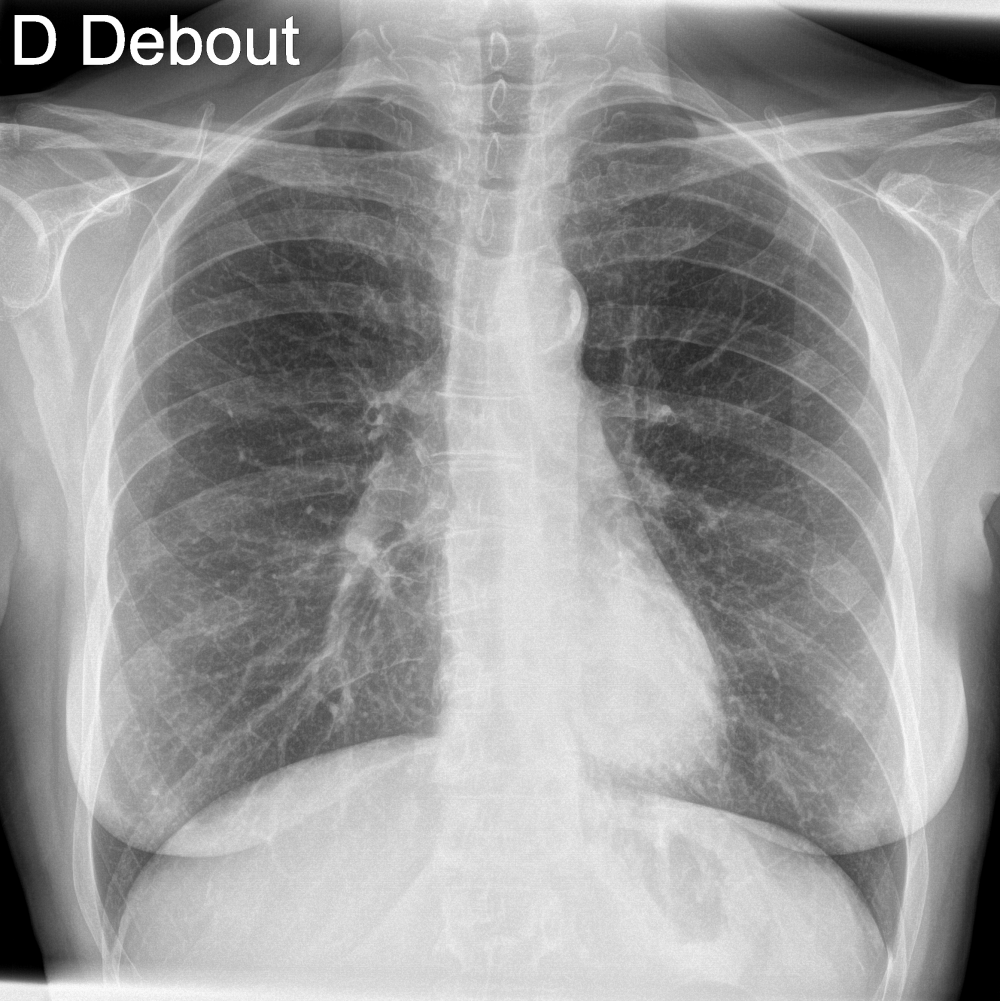

A 26-year-old male smoker with persistent cough.

ChestView detected a suspicious nodule, confirmed by CT.